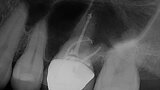

EdgeFile X7: Beastly bifurcation